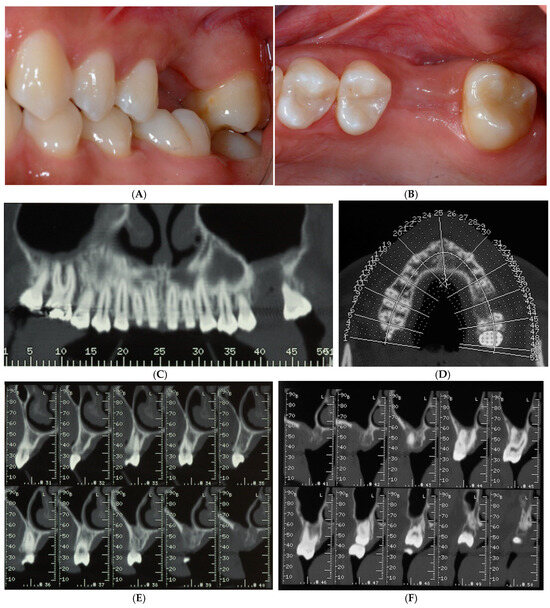

A 22-year-old healthy, non-smoker female patient presented with a chief complaint of recurrent infections of the first maxillary left molar due to a large osteolytic lesion caused by the failure of repeated endodontic therapies, as revealed by computed tomography (CT) scans (Figure 1A,B).

Figure 1.

Computed tomography (CT) scans revealed large osteolytic lesion of first maxillary left molar caused by failure of repeated endodontic therapies (A). Cross-sections showing buccal bone loss (B).

Treatment options were discussed, and the patient signed a consent form for the tooth extraction and the subsequent augmentation procedure, to be scheduled as a staged approach for implant site development. Four months after the tooth extraction, soft tissue healing reached a proper maturation (Figure 2A,B), and a new CT was requested to evaluate the wound healing and bone availability for implant therapy. The CT scans revealed a horizontal ridge defect (Figure 2C,D–F) that required correction with a staged GBR procedure.

Figure 2.

Soft tissue healing four months after tooth extraction (A,B). New CT was requested to evaluate wound healing and current bone availability for implant therapy. CT scans revealed horizontal ridge defect (C–F) that had to be corrected with a regenerative procedure.